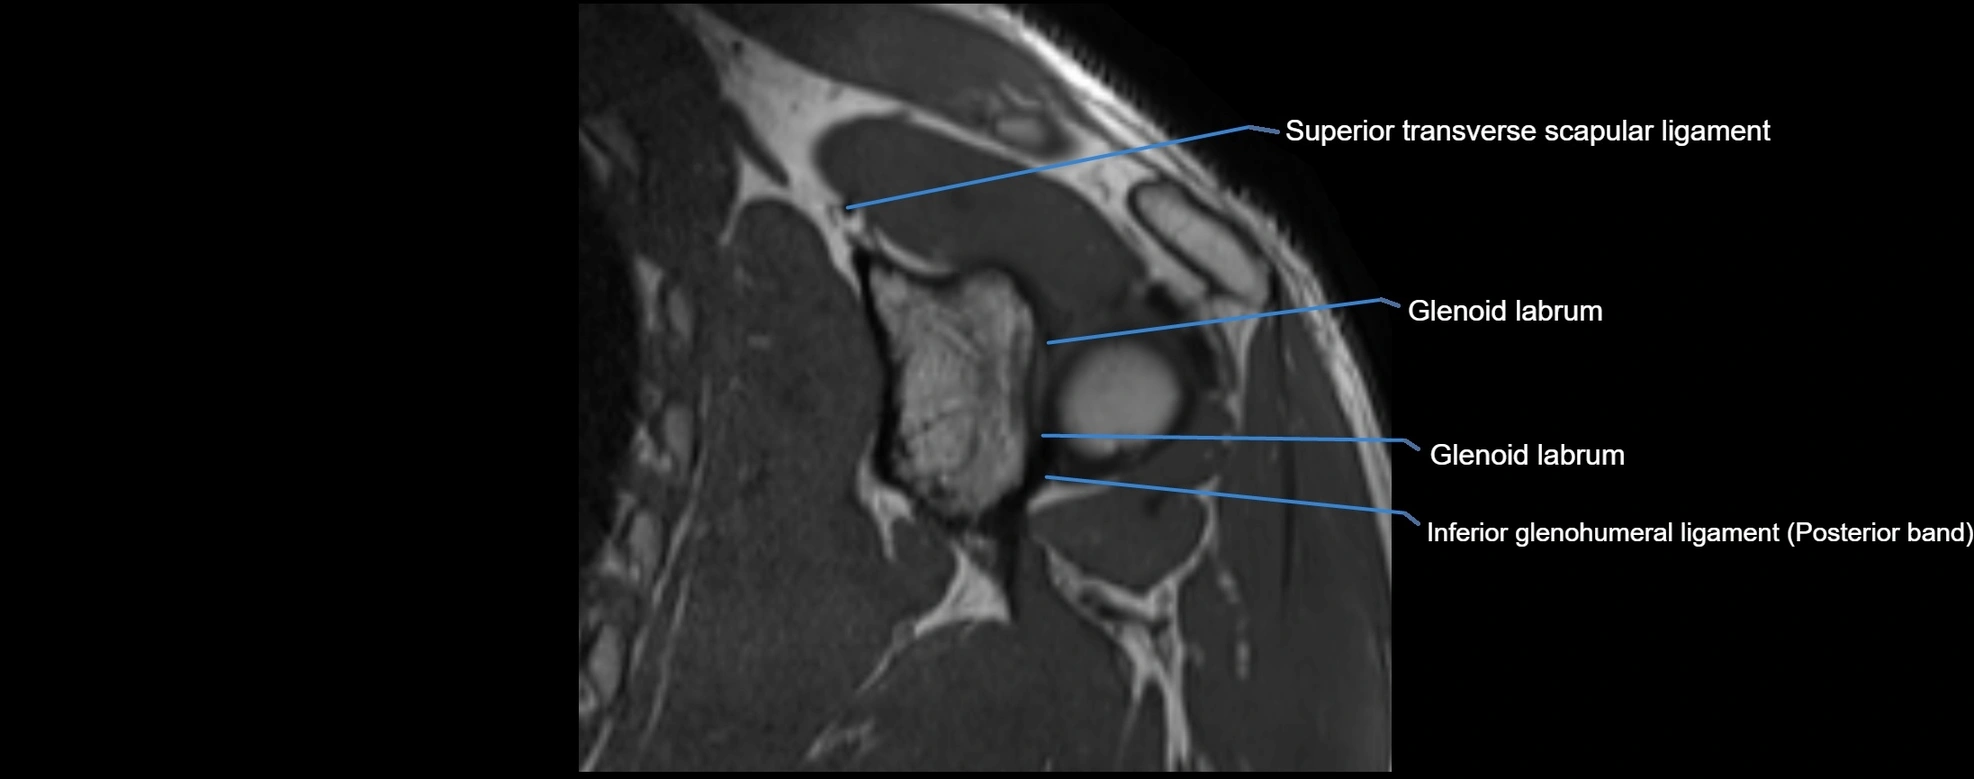

MRI images

image